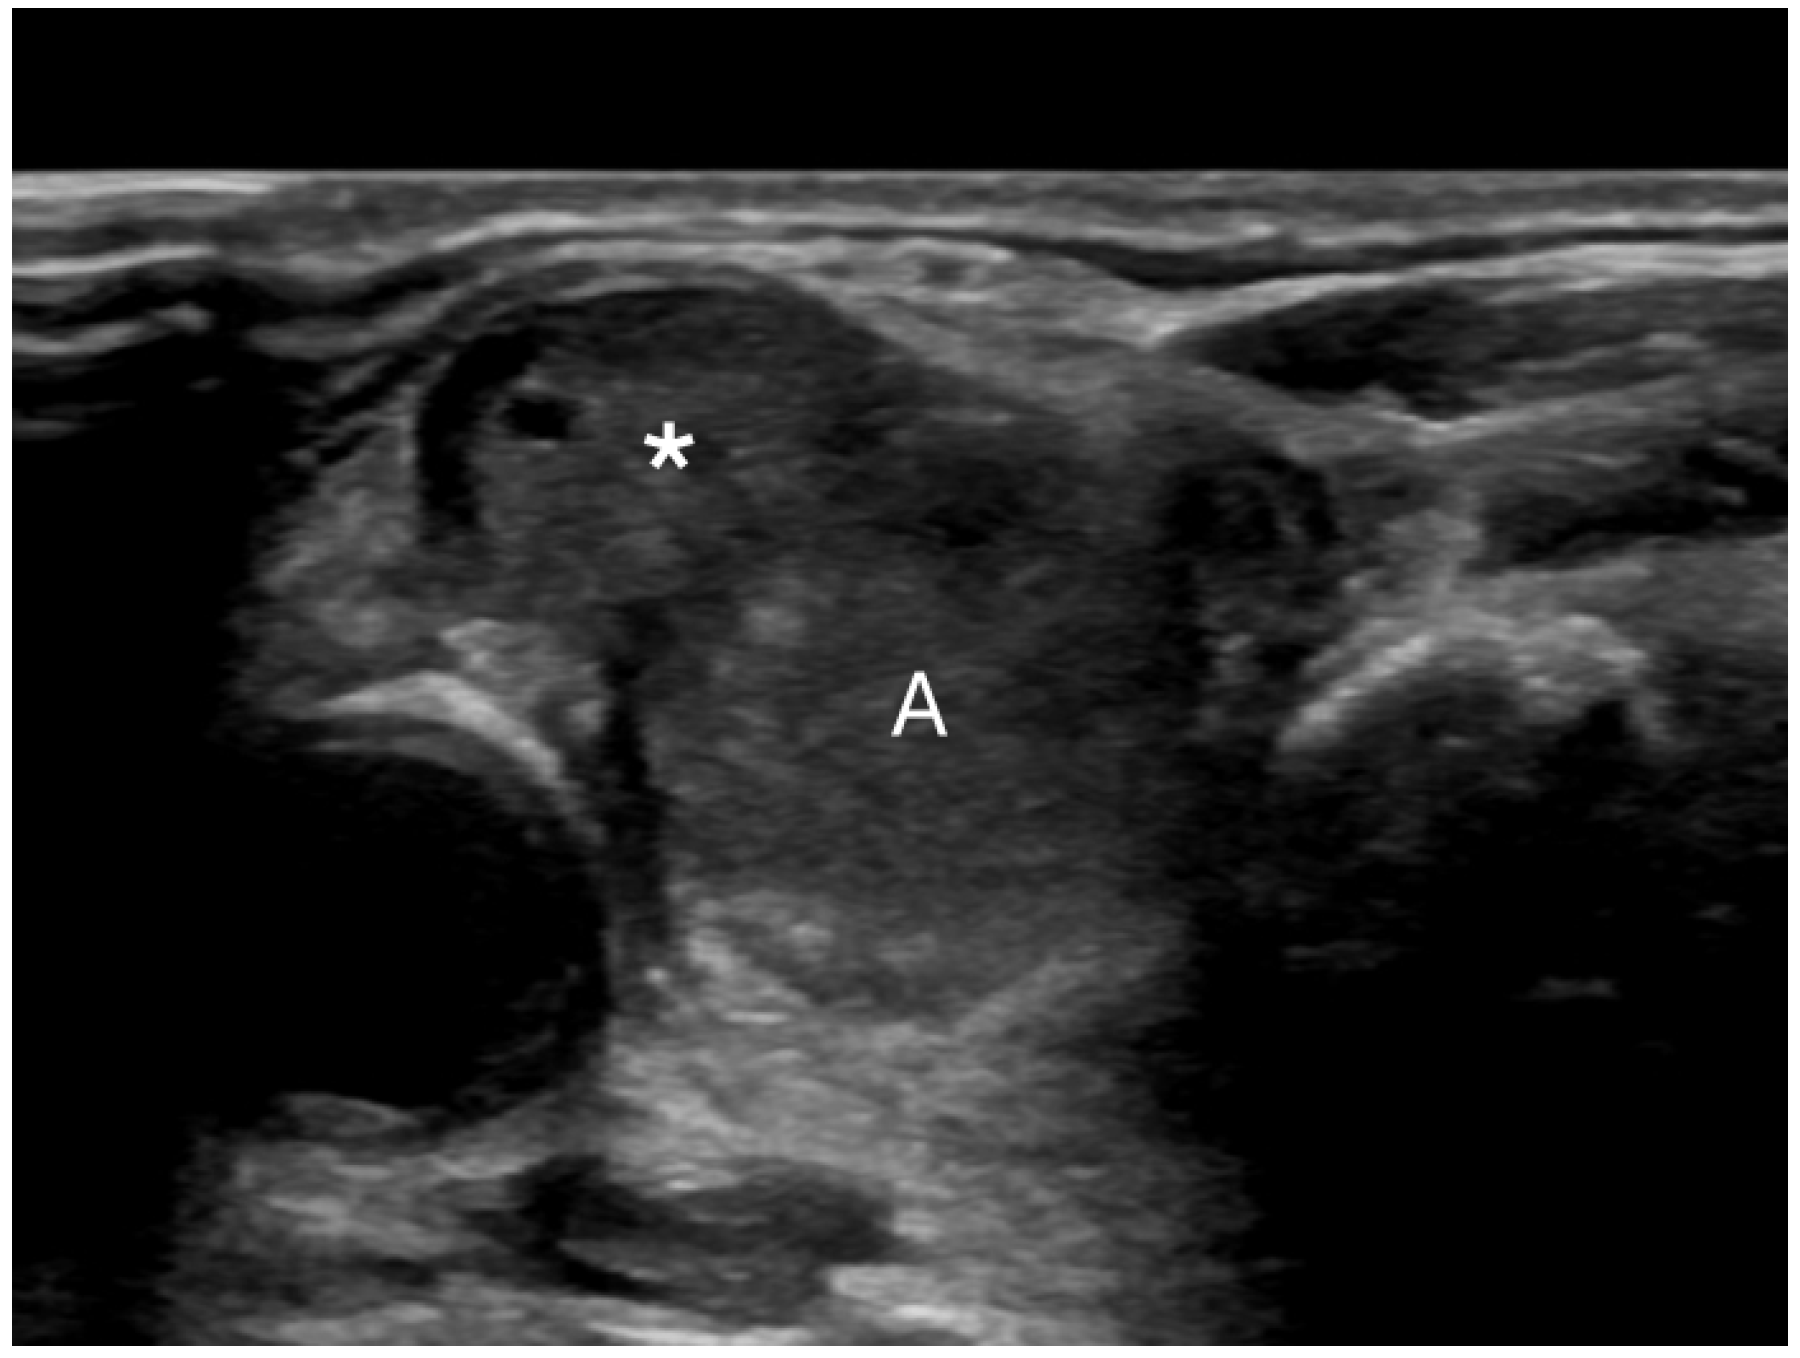

Figure 5. Extrathyroidal extension (*) extending anteriorly from a malignant nodule (A).

Extrathyroidal extension beyond the thyroid capsule into the surrounding soft tissues is reported in 5% to 34% of thyroid cancers and is a predictor of negative outcomes (Figure 5) [58,59,60]. Detecting minimal extrathyroidal extension, indicated by subtle capsular disruption, is challenging. Additionally, ill-defined benign nodules located near the thyroid capsule may cause focal bulging and capsular distortion, leading to false positives. Consequently, there is considerable interobserver variability in detecting extrathyroidal extension [61]. Lee et al. found that the combination of tumor disruption of the capsule—manifesting as a loss of the capsule’s outline—and >50% tumor contact with the capsule had 95.4% specificity, 23.7% sensitivity, and an AUROC of 0.64 for predicting extrathyroidal extension [25,62]. Our study found that 0.2% of benign nodules were misclassified as showing extrathyroidal extension. In contrast, extrathyroidal extension was found in 8.2% of malignant nodules. Overall, suspected extrathyroidal extension was associated with an OR for cancer of 27.2 (95% CI, 4.6 to 160), at p < 0.001.